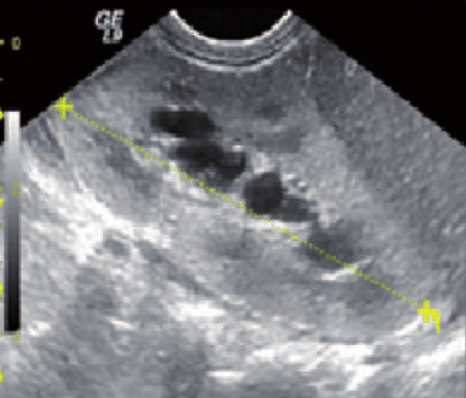

Este sistema se introdujo para proporcionar un enfoque unificado para describir la dilatación del tracto urinario en neonatos y lactantes jóvenes. Se clasifica en tres grados postnatales: UTD P1 (bajo riesgo), UTD P2 (riesgo intermedio) y UTD P3 (alto riesgo). Este sistema ha demostrado ser útil para predecir la necesidad de intervención quirúrgica y la ocurrencia de infecciones del tracto urinario (ITU) en neonatos con hidronefrosis.[1-3]

Este sistema clasifica la hidronefrosis en cuatro grados, de I a IV, basándose en la apariencia ecográfica del sistema colector renal. Los grados más altos están asociados con un mayor riesgo de intervención quirúrgica y menor tasa de resolución espontánea.[4-6]

0, no hydronephrosis / 1) dilatation of renal pelvis alone / 2) plus caliceal dilation / 3)plus< ½ renal parenchymal loss / 4)plus> ½ renal parenchymal loss.